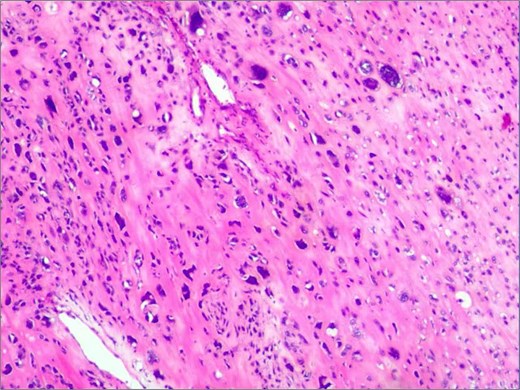

Histopathological analysis shows spindle cell tumor, combined with immunohistochemical results, conforms to high-grade sarcoma, considering extra bone osteosarcoma.

Histopathological analysis confirmed a high-grade extraskeletal osteosarcoma (FNCLCC Grade 3) with focal necrosis. Immunohistochemistry demonstrated strong positivity for SATB2 and osteocalcin. The patient recovered without complications and was discharged on postoperative day 12. At 6-month follow-up, she remained disease-free under adjuvant radiotherapy (Fig. 4).